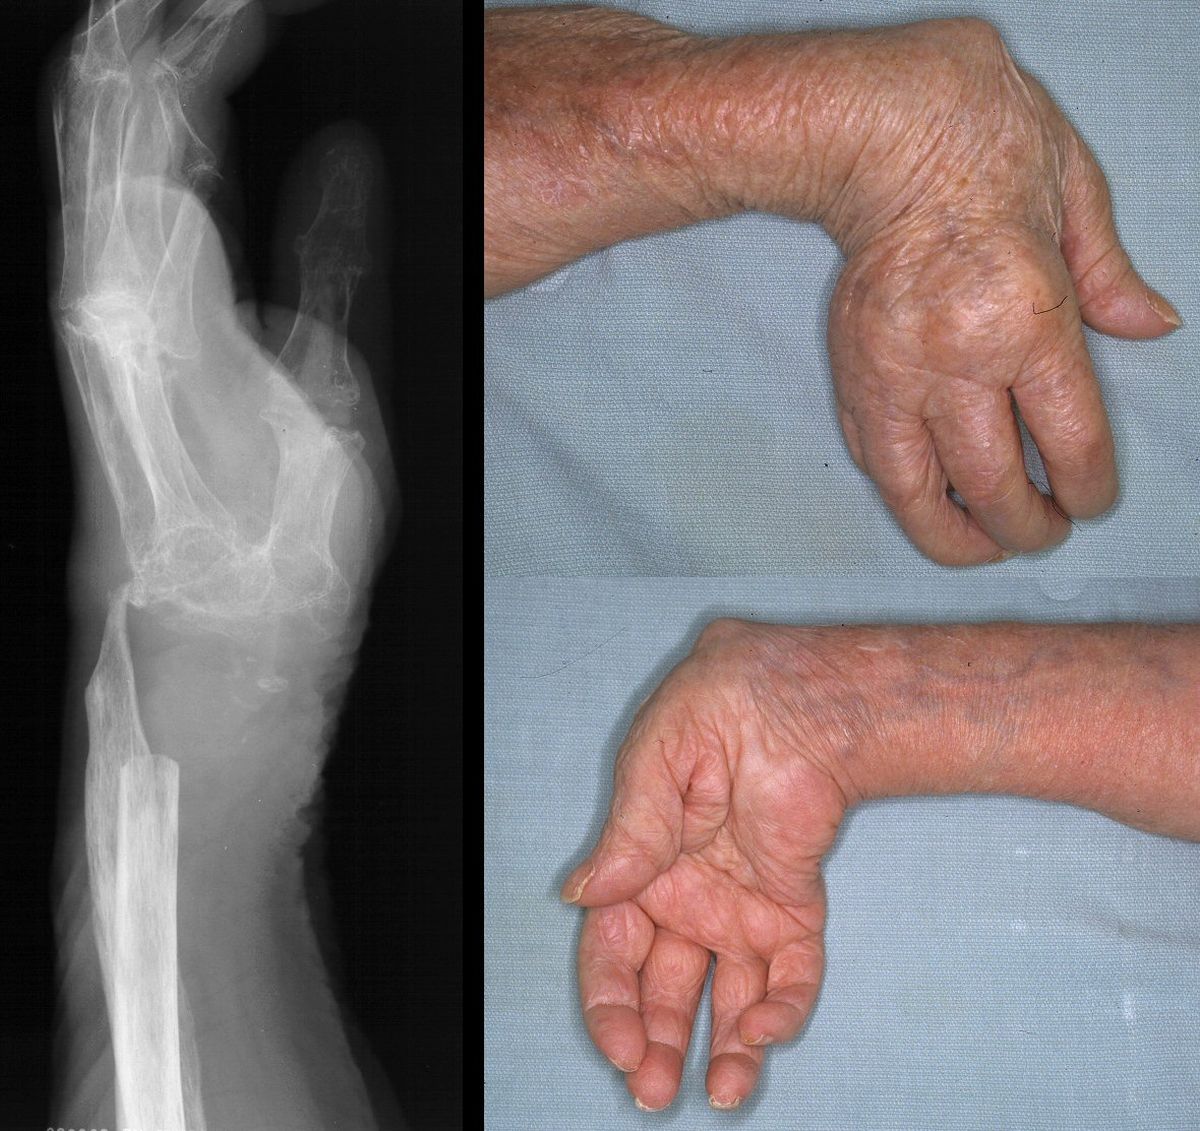

This senior woman presented with wrist swelling. She had been previously managed elsewhere with a Swanson flexible wrist arthroplasty, complicated by infection, which was treated with implant removal. She had done well for the last four years, but recently had swelling and tenderness of the wrist. Xrays showed a flail wrist with radiometacarpal impingement:

She was treated with splinting, and responded well. However, she returned four months later with a draining sinus from the distal ulna and evidence of osteomyelitis.

She was treated with radical resection of the infected bone. Intraoperative cultures grew out normal skin flora and she received 6 weeks of appropriate intravenous antibiotics.

There was no cinical evidence of residual infection. She maintained a functional range of motion from her pseudoarthrosis and did not wish to have any more surgery.

Four years later, she complained of wrist instability, and xrays confirmed intermittent radiometacarpal dislocation.